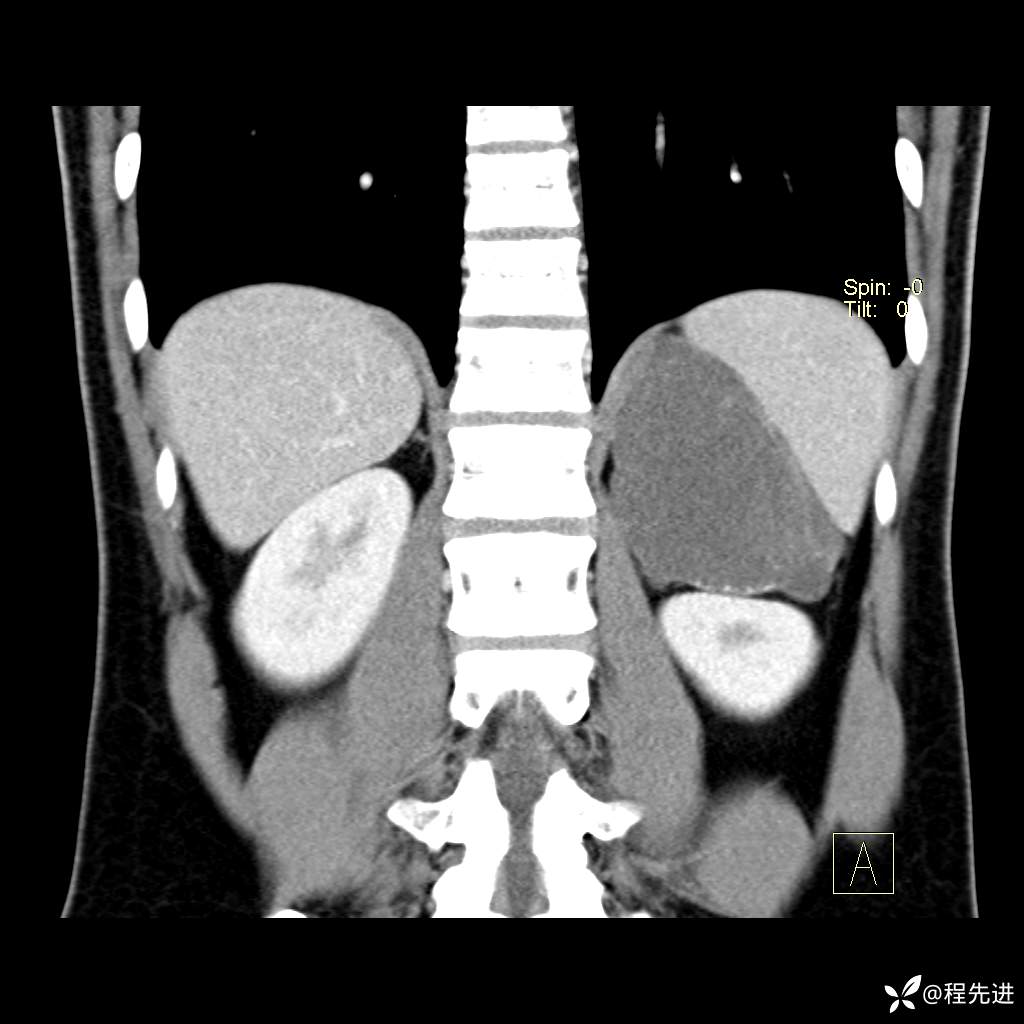

CT平扫:(CT值:平扫,27HU,动脉期,27HU,门静脉期,31HU,平衡期,32HU)

冠状位重建: